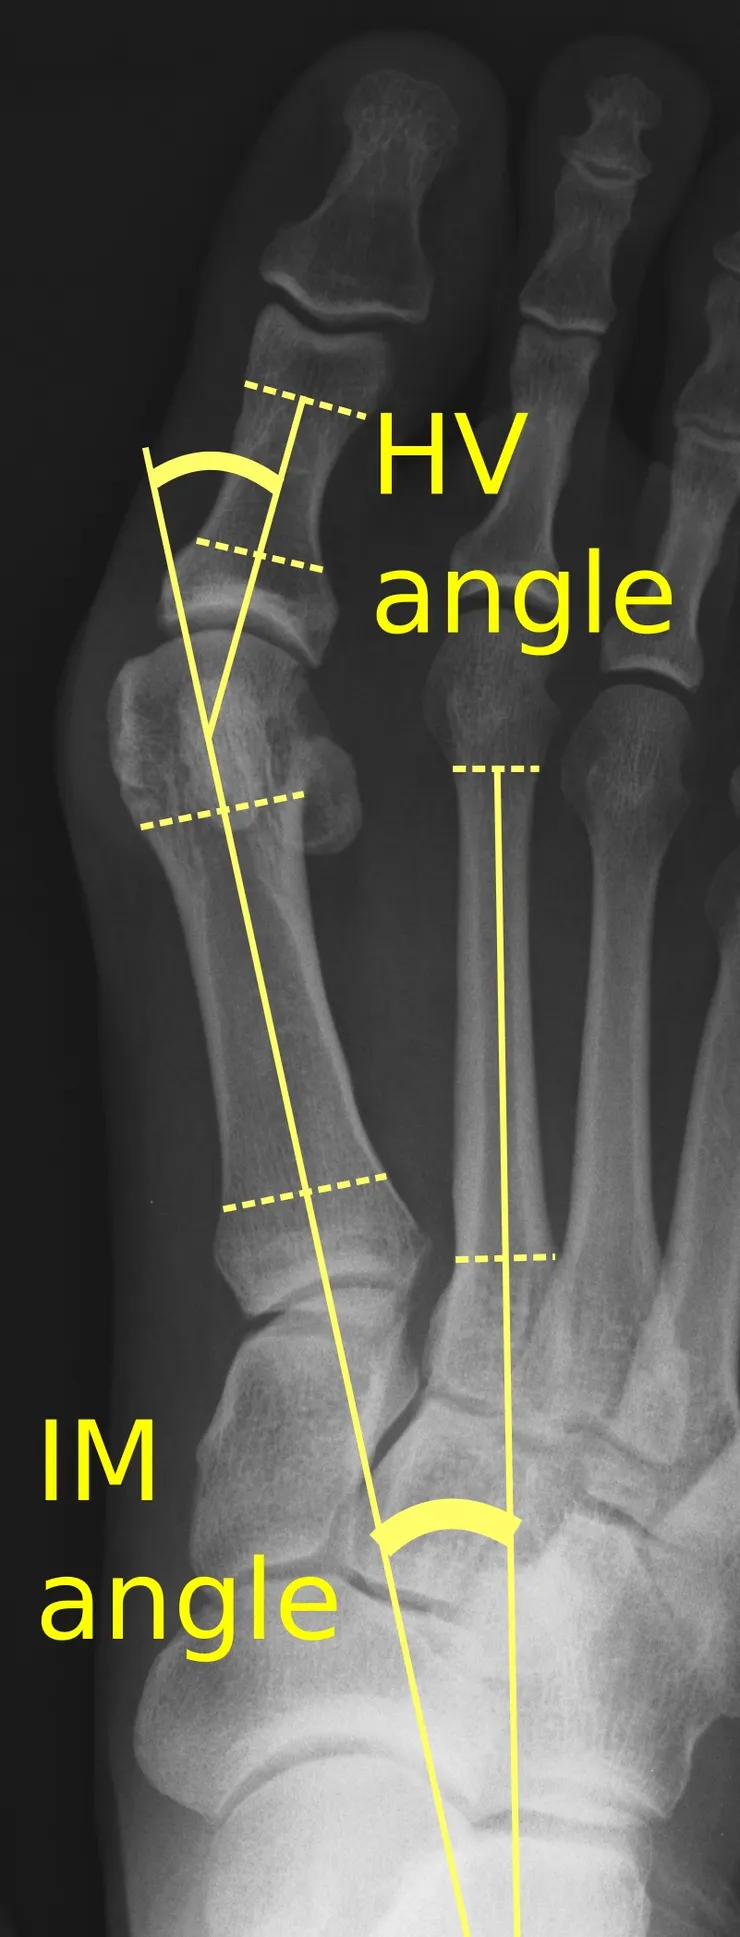

根據X光合併臨床症狀可分為輕、中、重度,通常在X光下會量測拇趾縱軸和第一蹠骨縱軸的交角(HA),一般來說小於15-20度是屬於正常(其實一般人有輕微外翻是正常的喔!),大於30度則是極有可需要手術治療的重度拇趾外翻